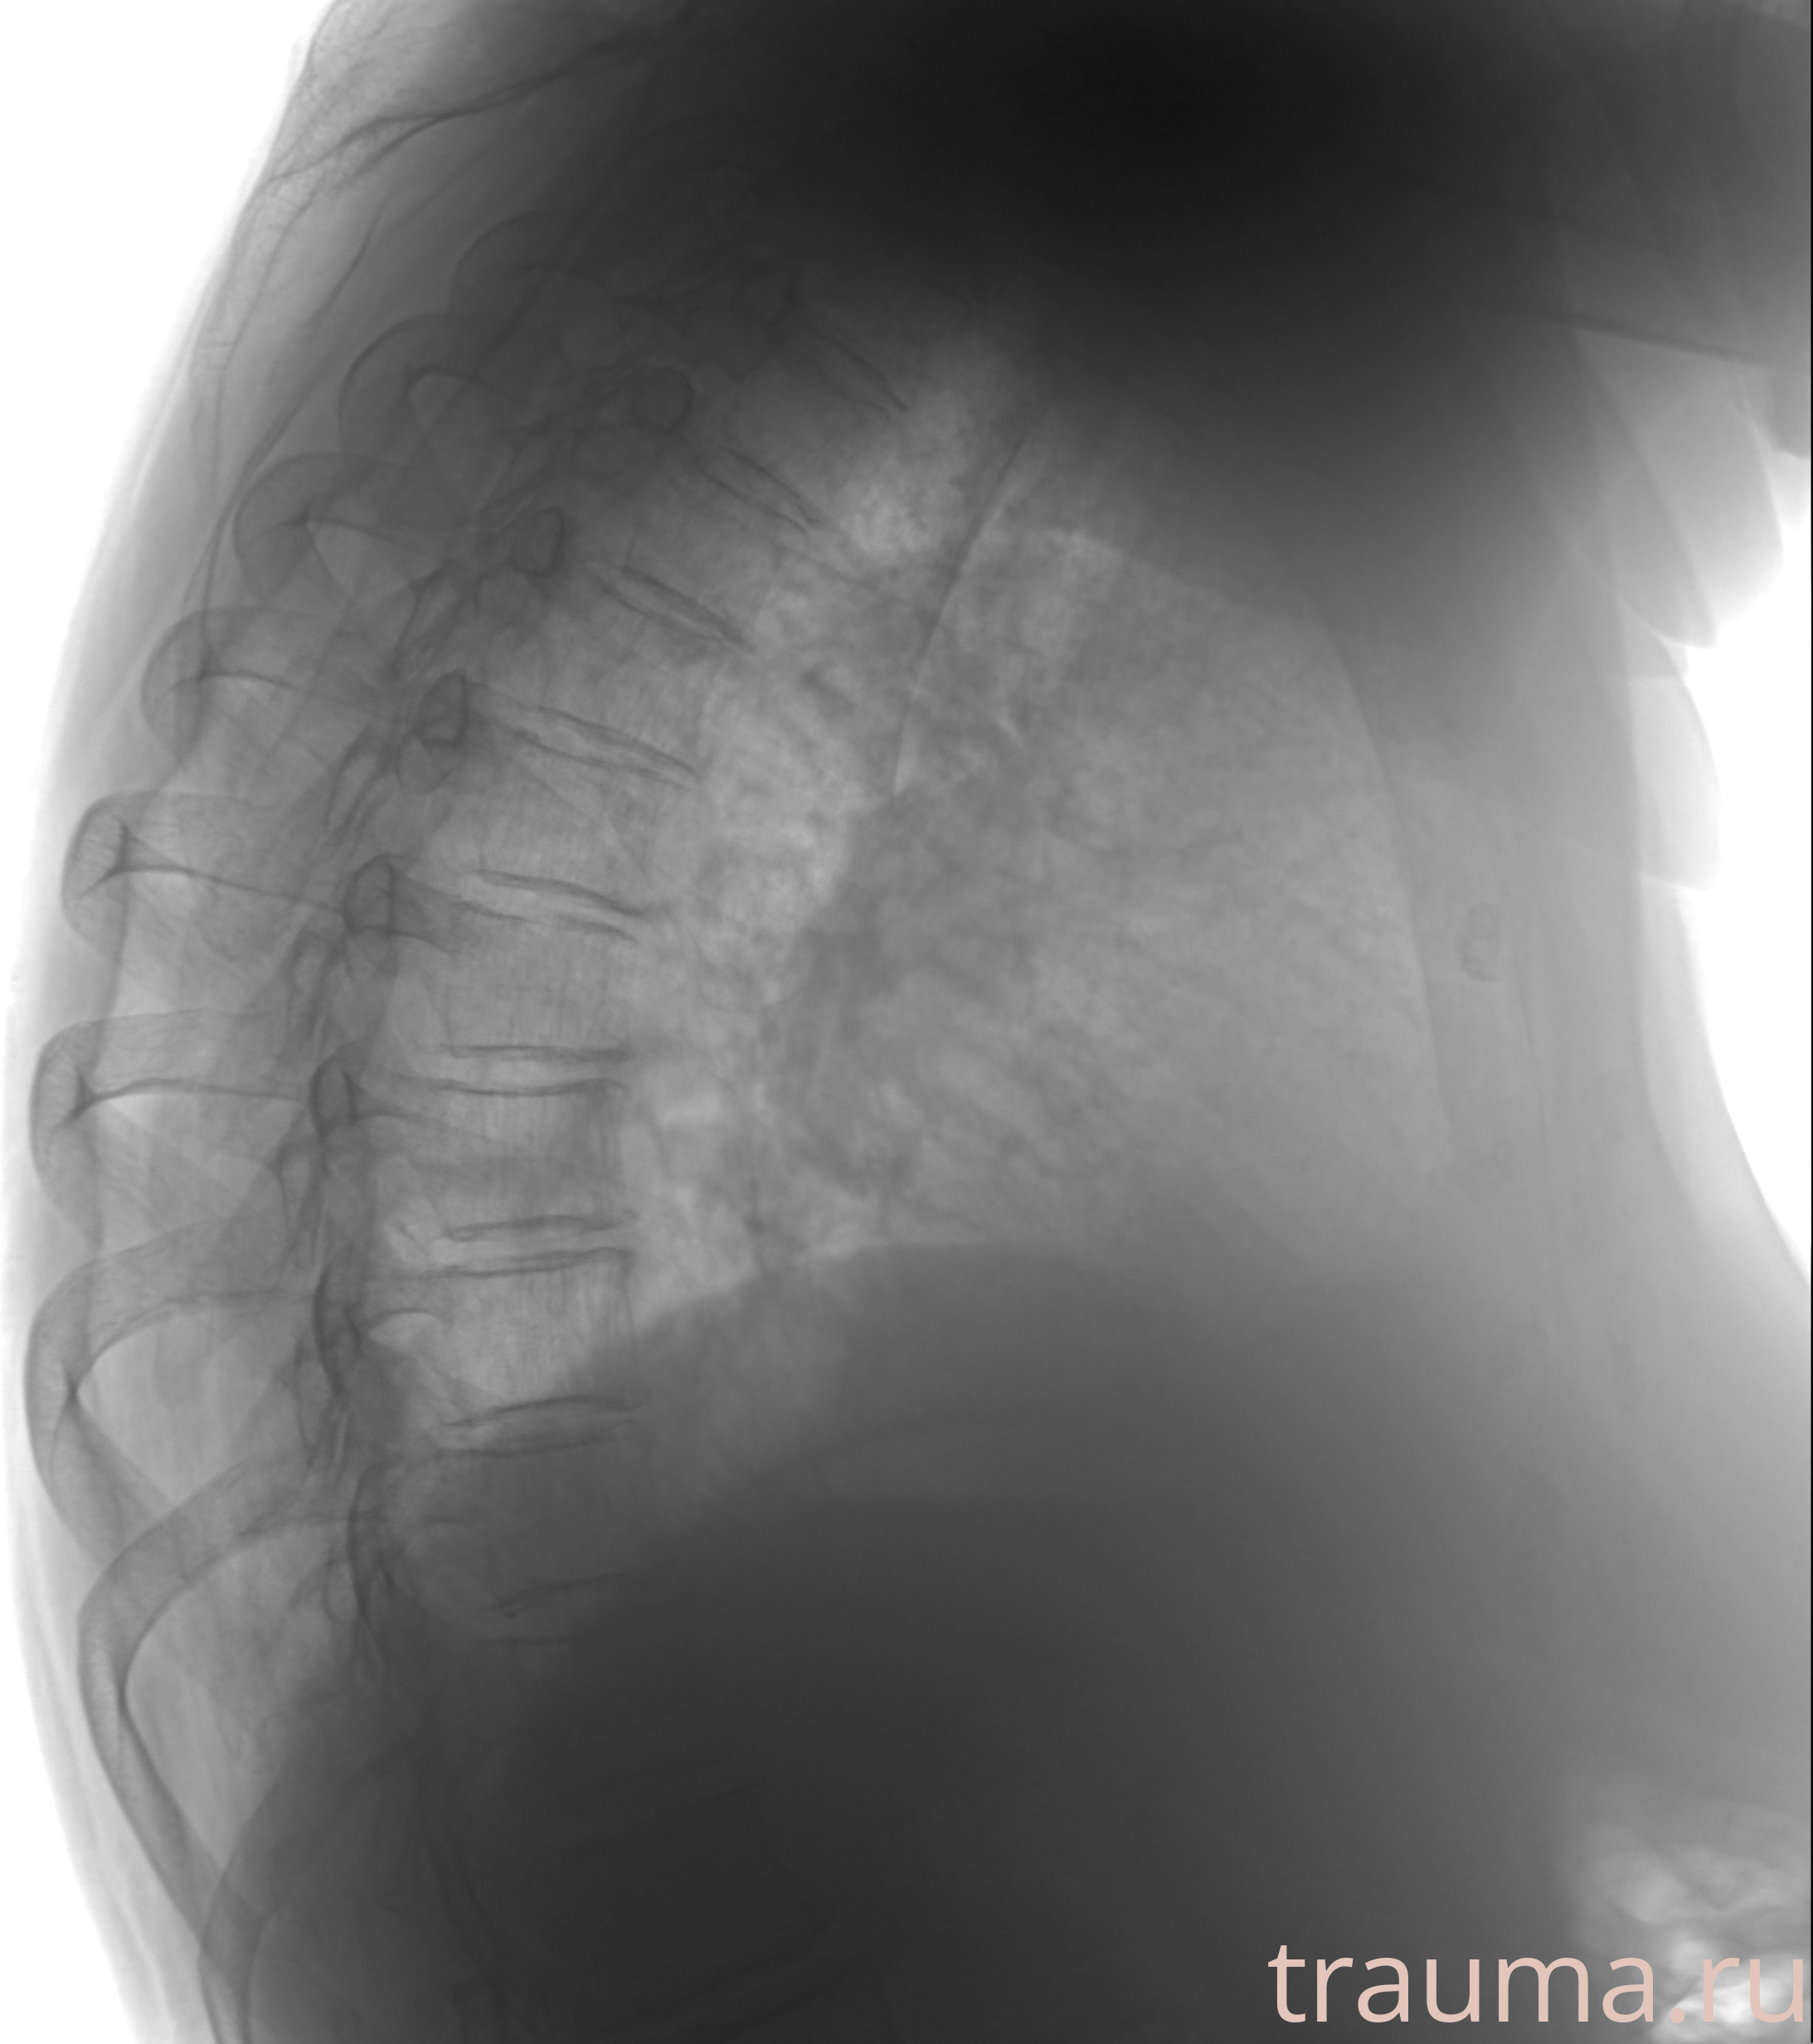

Рентгенограммы

Рентген на дому: по вашему адресу приезжает врач-рентгенолог, травматолог-ортопед с мобильным рентгеновским аппаратом, проводит диагностику травмы или заболевания, делает необходимые рентгенограммы, дает рекомендации по дальнейшему лечению. Получить качественные снимки в домашних условиях возможно благодаря уникальной методике, разработанной МосРентген Центром для института  Склифосовского